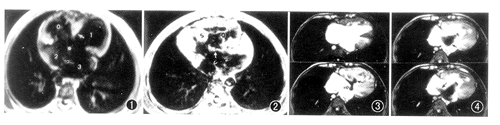

全组病例心脏各个房室腔均有增大,6例以右心房室扩大为著,伴有右心室壁增厚,2例以左心房室增大为著,心内膜垫结构消失,4个心腔呈“十”字形直接相通,形成室间隔膜部和I孔型房间隔缺损,二、三尖瓣的结构不完整(图1)。上述征象在体轴横断面和垂直室间隔的左室长轴断面像上显示得最清楚。8例患者中有6例主肺动脉扩张,其内径平均为(25.2±3.0)mm,大于升主动脉内径[平均(20.5±3.6)mm],余2例有右室流出道、主肺动脉及左右肺动脉的狭窄,并存升主动脉骑跨在室间隔缺损之上,提示CTECD与Fallot四联症并存。全组有4例合并主动脉右弓右降,合并右旋心(图2)和永存左上腔静脉与冠状静脉窦相通各1例。

GE电影MRI直接显示了左、右房室之间的分流和心室向心房的返流(图3,4)。舒张末期4个心腔之间无血流交通,收缩早期左心室部分血液经室间隔膜部缺损向右心室喷射,同时右心室血液经共同房室瓣向左心房内喷射(图3),收缩中晚期右心室向左心房的返流量加大,并经I孔型房间隔缺损由左心房向右心房喷射(图4)。

图1 SE脉冲序列体轴横断面T1WI显示:心脏各个心腔均有扩大,心内膜垫正常结构消失(.),导致二、三尖瓣结构不完整,室间隔膜部缺损和I孔型房间隔缺损。0:右心室,1:左心室,2:右心房,3:左心房,↑:II孔房间隔,←:肌部室间隔 图2 SE脉冲序列体轴横断面T1WI显示:右旋心,左心室和心尖位于右侧胸腔,心内膜垫正常结构消失,形成膜部室间隔缺损和I孔型房间隔缺损,可见1个大的共同房室瓣。S:室间隔,↑:共同房室瓣,<:房间隔,0:右心室,2:右心房 图3,4 梯度回波(GE)脉冲序列电影MRI垂直室间隔长轴断面像:图3上为舒张末期像,见心内膜垫结构消失,4个心腔直接相通连。图3下为收缩早期像,显示血液由左心室经膜部室间隔缺损向右心室分流(←),同时右心室的血液向左心房返流(

)。图4上为收缩中期像,见右心室向左心房的返流量加大,并向右心房分流(

)。图4下为收缩中晚期像,显示左心房的血液经房间隔缺损向右心房分流(

)